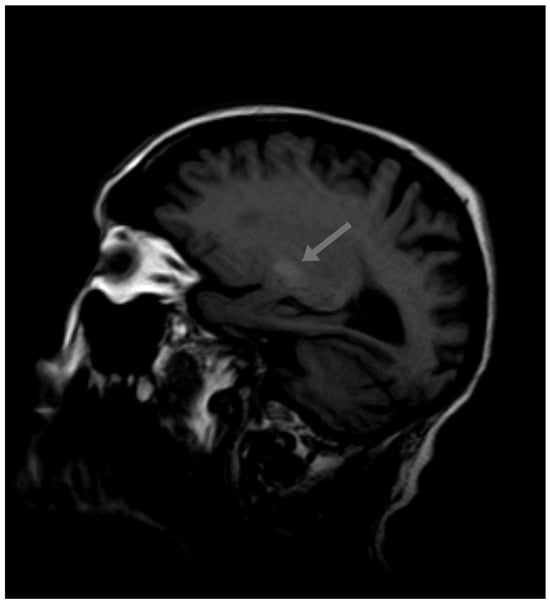

2. Case Report

2.2. Current Disease

2.3. Additional Tests